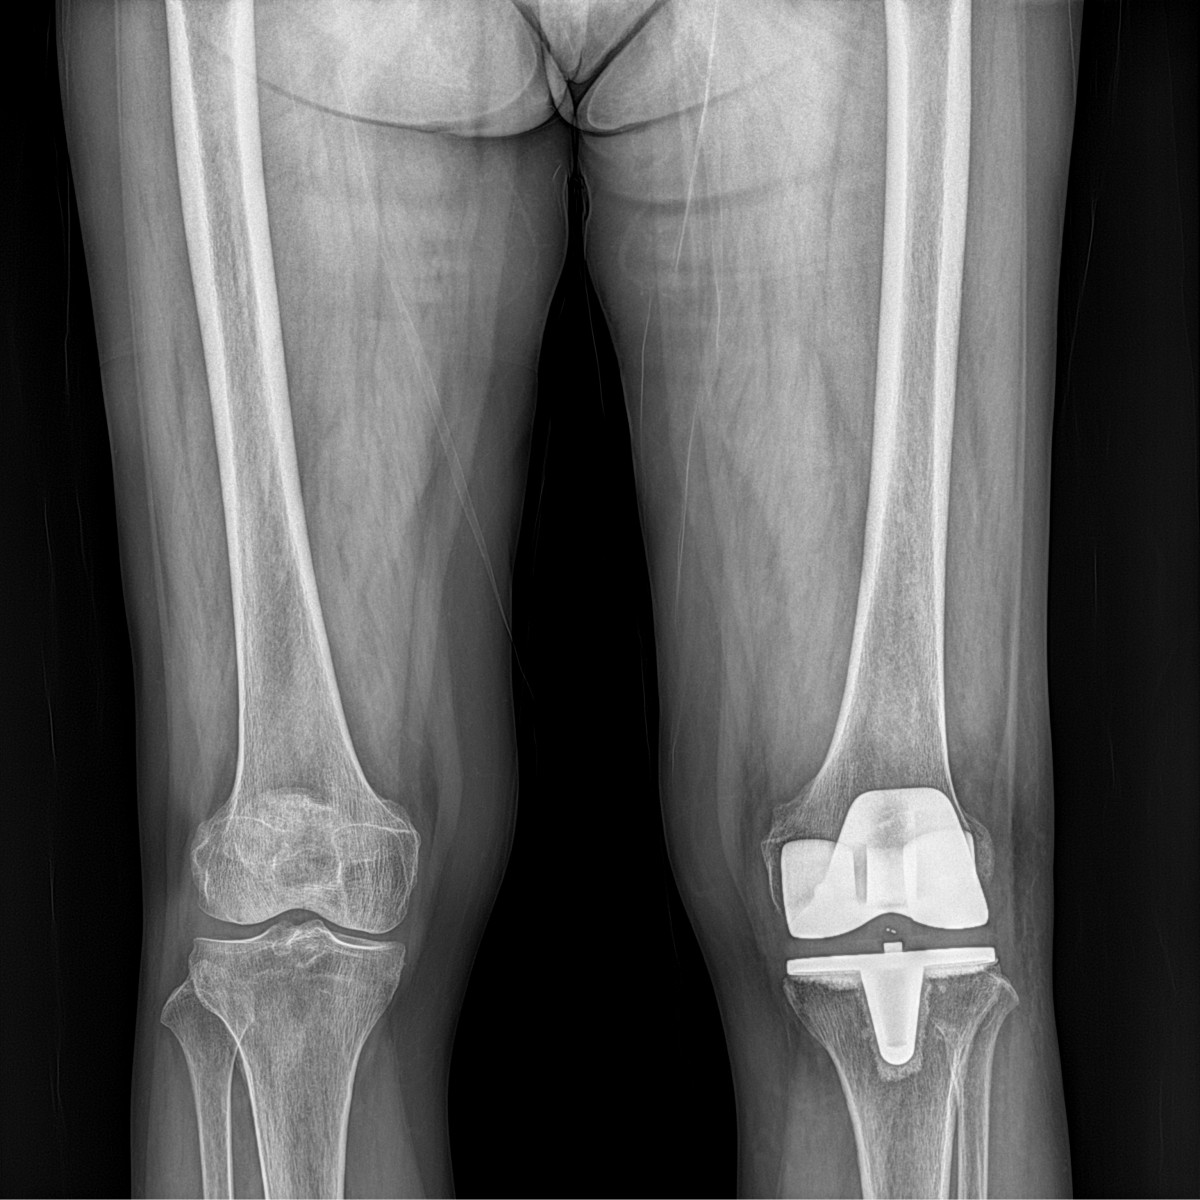

이재상원장님 무릎 인공관절 치환술 이석O 환자

작성자 최고관리자 댓글 0건 조회 702회 작성일 25-09-16 17:12

dae765e4d9ac96aee867c9d6292d8784_1758010372_4764.jpg